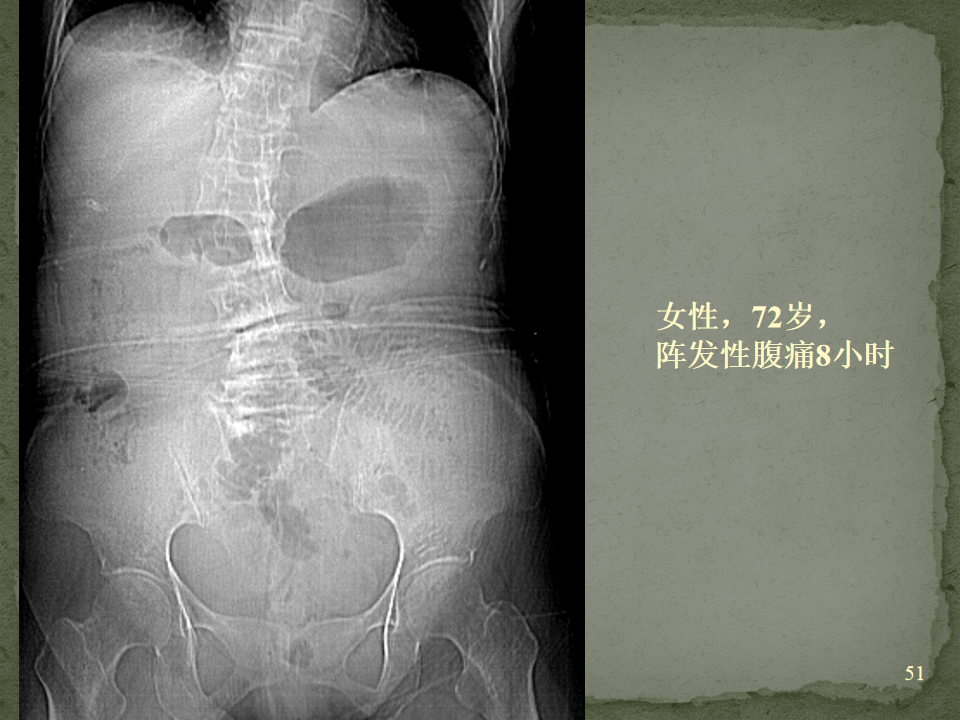

[腹盆] 肠梗阻的CT影像诊断

肠梗阻的CT影像诊断